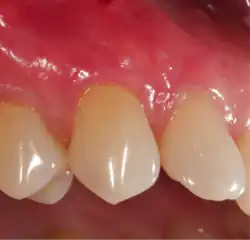

Exposure of the tooth root due to loss of keratinized tissue around the neck of a tooth is referred to as gingival recession. This can result in sensitivity or pain from the exposed tooth root surface (dentin is more permeable and soft compared to enamel and dentin is what makes up the tooth root).[6] Recession may also cause an unasthetic appearance especially if located in the anterior dentition (front teeth). While not all cases of gingival recession require surgical correction, there are various options if that is what the patient desires.[7] It should be reinforced that recession left untreated will not result in tooth loss, contrary to popular belief. Also, recession that is left untreated can be maintained and the inflammation kept at bay with proper brushing and oral hygiene technique.[4] On the other hand, if one desires to pursue corrective therapy, there are a wide variety of techniques ranging from autograft (one's own tissue, usually taken from the palate), allograft (another's tissue, cadaver tissue), xenograft (animal tissue, usually porcine or bovine) or simply repositioning of the tissue native to the site.[8]

Gum grafting, also known as a gingival graft or periodontal plastic surgery, is a surgical procedure to reverse gum recession. Gum recession exposes the roots of teeth,[9] which can lead to sensitivity and put teeth at a higher risk of damage or disease[10] due to the loosening of their attachment within the gums and bones of the jaw. Should gum recession continue, bone and keratinized tissue will be at greater risk of being damaged and permanently lost around the teeth. The aim of a gum graft is to extend keratinized tissue of the gums to cover tooth roots,[11] which restores their firm placement within the jaw and prevents further damage.

A free gingival graft is a dental procedure where a small layer of tissue is removed from the palate of the patient's mouth and then relocated to the site of gum recession. It is sutured (stitched) into place and will serve to protect the exposed root as living tissue. The donor site will heal over a period of time without damage. This procedure is often used to increase the thickness of very thin gum tissue.

A subepithelial connective tissue graft takes tissue from under healthy gum tissue in the palate, which may be placed at the area of gum recession. This procedure has the advantage of excellent predictability of root coverage,[19] as well as decreased pain at the palatal donor site compared to the free gingival graft. The subepithelial connective tissue graft is a common procedure for covering exposed roots.